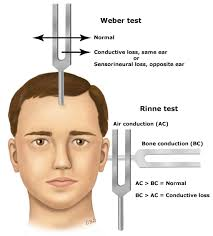

♦ weber and rinne test (વેબર અને રિન ટેસ્ટ)

◘ Bone conduction hearing test : =

Rinne Test-રિન ટેસ્ટ

- આ ટેસ્ટમાં વાઇબ્રિટીંગ ટ્યુનિક ફોર્ક ને ઈયર ની પાછળ mastoid process પર પ્લેસ કરવામાં આવે છે માસ્ટરોઈડ પ્રોસેસ ઉપર જો પેશન્ટની વાઇબ્રેશન લાંબા સમય સુધી ફીલ ન થાય તો ટયુનિક ફોર્ક ને ઈયરની આગળ બાજુ રાખવામાં આવે છે જો પેશન્ટ એ રિંગિંગ સાઉન્ડ સાંભળવા માટે એબલ ન હોય તો તે કાનમાં પેશન્ટને કંડક્ટિવ હેરિંગ લોસ છે તેમ કહી શકાય.

weber Test-વેબર

વધારેમાં ટ્યુનિક ફોર્ક ને ફોરહેડ પર રાખવામાં આવે છે.પછી પેશન્ટને પૂછવામાં આવે છે કે અવાજ એ ફોરહેડના વચ્ચેના ભાગમાં hearing થાય છે કે નહીં.અથવા બંને કાનમાં જોરથી અવાજ સંભળાય છે.

- જો પેશન્ટ ને conductive hearing loss હશે તો અફેક્ટેડ કાનમાં વધુ અવાજ સંભળાશે.

- જો પેશન્ટ ને sensorineural hearing loss તો તે કાનમાં ઓછો અવાજ સંભળાશે.

- આ ટેસ્ટ એ ઓડિયોલોજીસ્ટ ને કયા પ્રકારનું લોસ છે તે હશે જ કરવા માટે કરવામાં આવે છે.

- In conductive hearing loss ( caused by problem in the outer or middle ear),

- In sensorineural hearing loss ( caused by problem in the cochlea, the sensory organ of hearing)

- Or neural ( caused by a problem in the auditory nerve or auditory pathway of the brain).